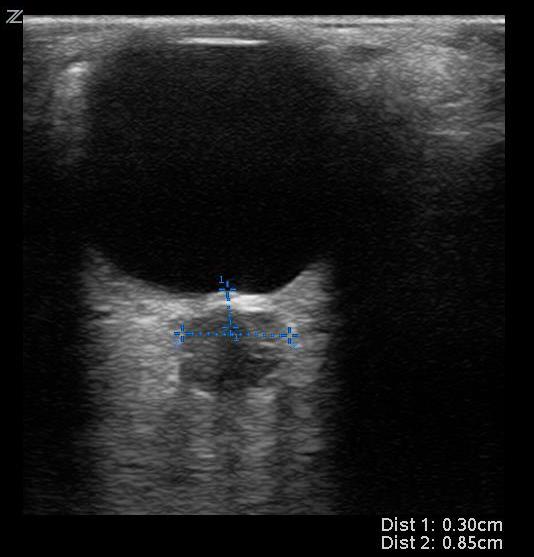

- On ultrasound, a normal optic nerve sheath measures up to 5.0 mm in diameter. The ONSD is measured 3mm posterior to the globe for both eyes.

- A position of 3mm behind the globe is recommended because the ultrasound contrast is greatest, and the results are more reproducible.

- Two measurements are averaged.

- An averaged ONSD > 5 mm in adults is considered abnormal and elevated ICP should be considered.4

- Figure 11. Example of increased optic nerve sheath diameter. Optic nerve sheath diameter > 5mm is considered abnormal and should raise concern for elevated intracranial pressure.